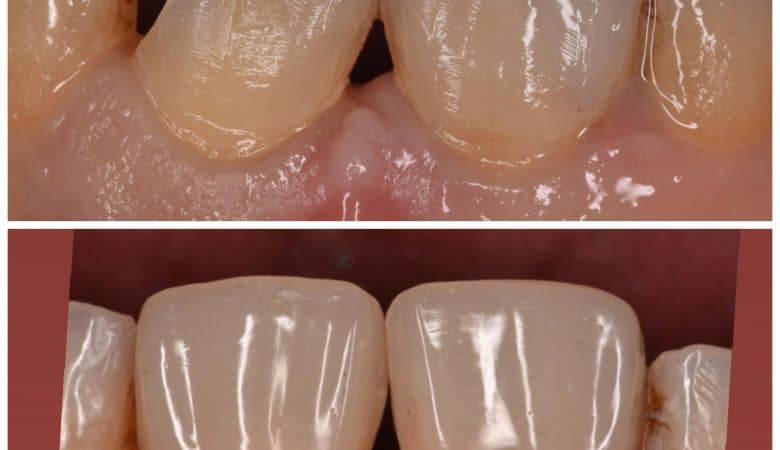

55 years old Diabetic pateint come to clinic asking for restoring her left central incisor ,so when I look for her centrals I offer her to fix them both not only the left central She was old diabetic patient with…